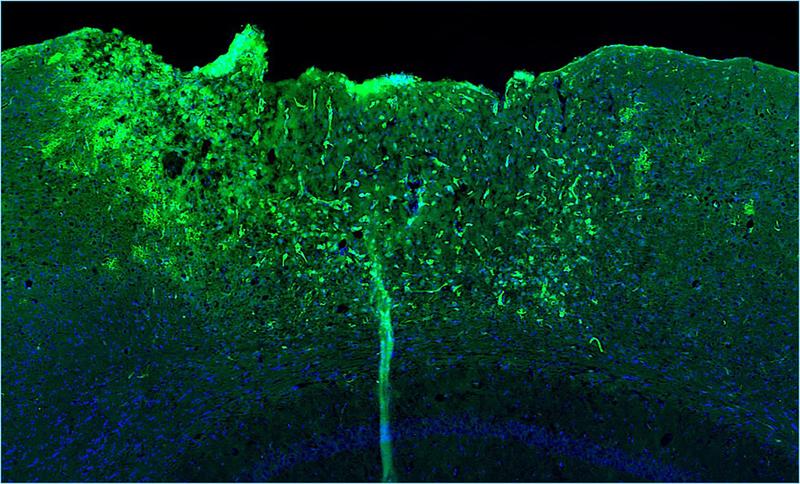

Die sternförmigen Gliazellen spielen außerdem eine Schlüsselrolle bei der Vernarbung von verletztem Hirngewebe. „An der geschädigten Stelle umschließen Astrozyten den Wundkern. So begrenzen sie weitere neurodegenerative Prozesse und unterstützen die Heilung“, erläutert Professorin Leda Dimou. Die Leiterin der Abteilung Molekulare und Translationale Neurowissenschaften an der Klinik für Neurologie war an der Studie federführend mitbeteiligt. In unmittelbarer Nähe der Verletzung fanden die Forschenden eine auffällige Genexpressionssignatur – ein Hinweis auf eine besonders hohe Aktivität von NF-κB in Astrozyten. Um den Einfluss dieses Genschalters genauer zu untersuchen, arbeiteten die Forschenden mit Mausmodellen. In diesen war NF-κB in Astrozyten entweder dauerhaft aktiviert oder stark gehemmt. Das Team wollte wissen: Verbessert oder verschlechtert sich dadurch die Heilung nach einer traumatischen Hirnverletzung?

Das Ergebnis fiel eindeutig aus: War NF-κB dauerhaft aktiv, reagierte das Immunsystem schneller und stärker auf die Verletzung. Diese überschießende Neuroimmunantwort löste Entzündungsprozesse aus und störte sowohl Wundheilung als auch Narbenbildung.

„In den Wundbereich wanderten plötzlich auch bestimmte Immunzellen wie dendritische Zellen ein. Dadurch konnte sich kein stabiles Narbengewebe bilden, was schließlich zu neurologischen Defiziten führte“, berichten die Erstautorinnen der Studie, Tabea M. Hein und Ester Nespoli. Erstaunlich: Ganz ähnliche Prozesse zeigen sich im alternden Gehirn. Wurde NF-κB in Astrozyten dagegen gehemmt, waren einzelne positive Effekte zu beobachten: So verbesserten sich die antioxidative Abwehr und die Funktion der Mitochondrien. „Diese Veränderungen reichten jedoch nicht aus, um den Heilungsprozess insgesamt deutlich zu verbessern“, erklären die Forschenden.